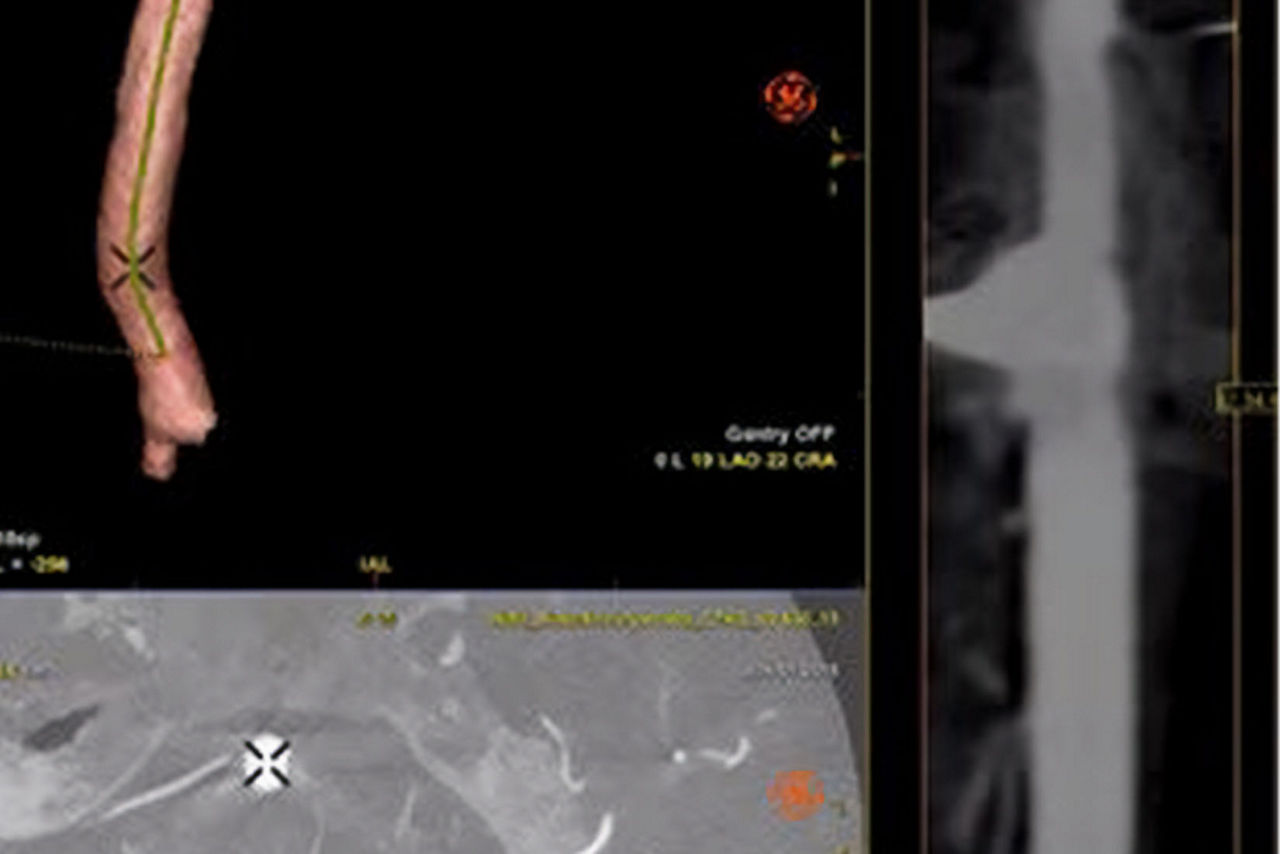

Plan

Automatically extract the bone and vessel anatomies. Edit vessel centerlines and bridge them through occlusions.

Plan

Segment and size the anatomy of interest in CBCT.1 Plan the stent positioning on the 3D model and prepare 3D landmarks to help guide the deployment.